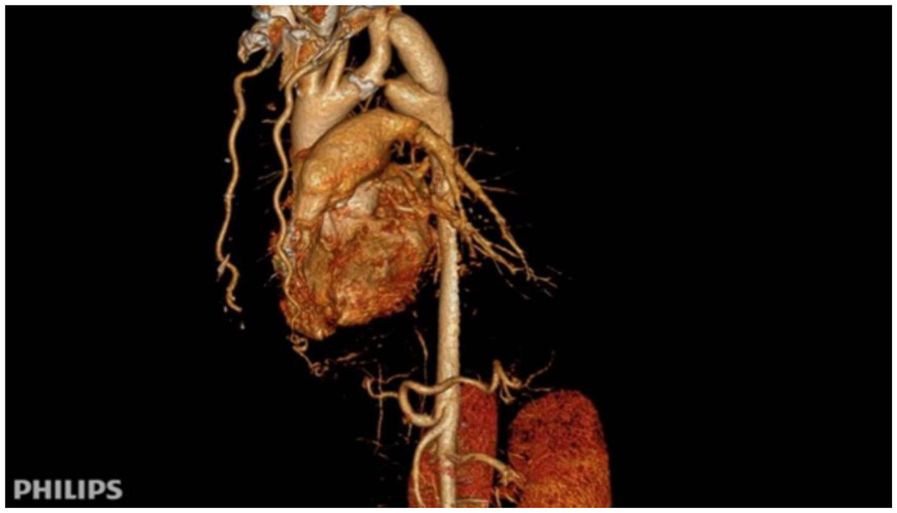

After surgery, the patient's antihypertensive regimen was gradually reduced in a stepwise fashion. At discharge, only metoprolol was continued, and both nifedipine and sacubitril/valsartan were discontinued. Postoperative blood pressure measurements were balanced across all four limbs: 115/69 mmHg (right upper limb) and 126/75 mmHg (left lower limb). Follow-up CTA confirmed satisfactory graft patency and flow (Figure 3).

Figure 3

Immediate postoperative CTA following subclavian-to-descending aorta bypass. Patency of the synthetic vascular graft (Dacron) from the left subclavian artery to the descending aorta is demonstrated, with normalization of the aortic lumen distal to the coarctation.